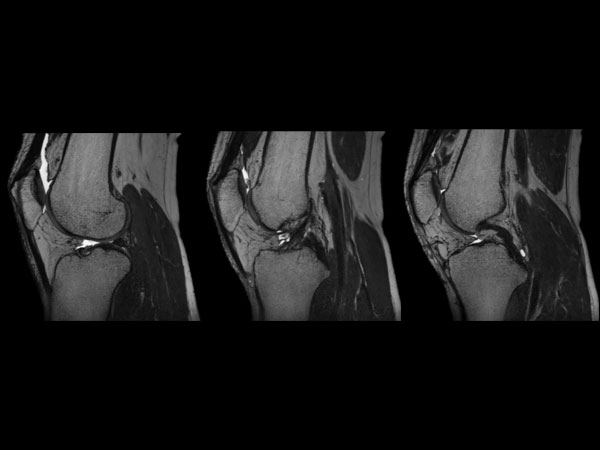

3D Knee imaging with MSK VIEW